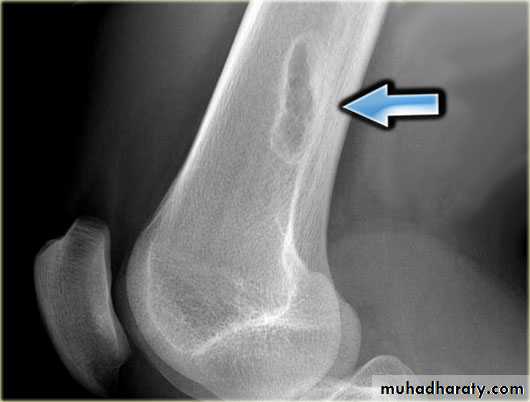

4.Periosteal reaction

the causes of localized peiosteal reactions adjacent to a lytic or sclerotic lesions are :

.Osteomyelitis.Malignant bone tumour , particularly Ewing sarcoma & osteosarcoma